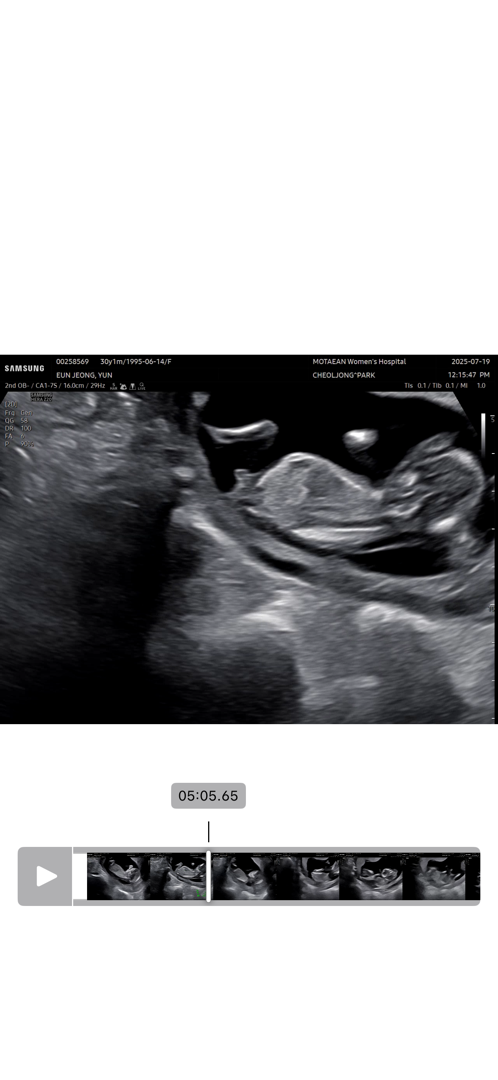

13주차 쌍둥이 각도법 잘보시는분!!

자연임신 일란성 쌍둥이입니다~ 의사쌤이 여아 일꺼같다고 말씀하시는데 아직은 정확하지는 않다고 하셔서 궁금해서 올려봐요!